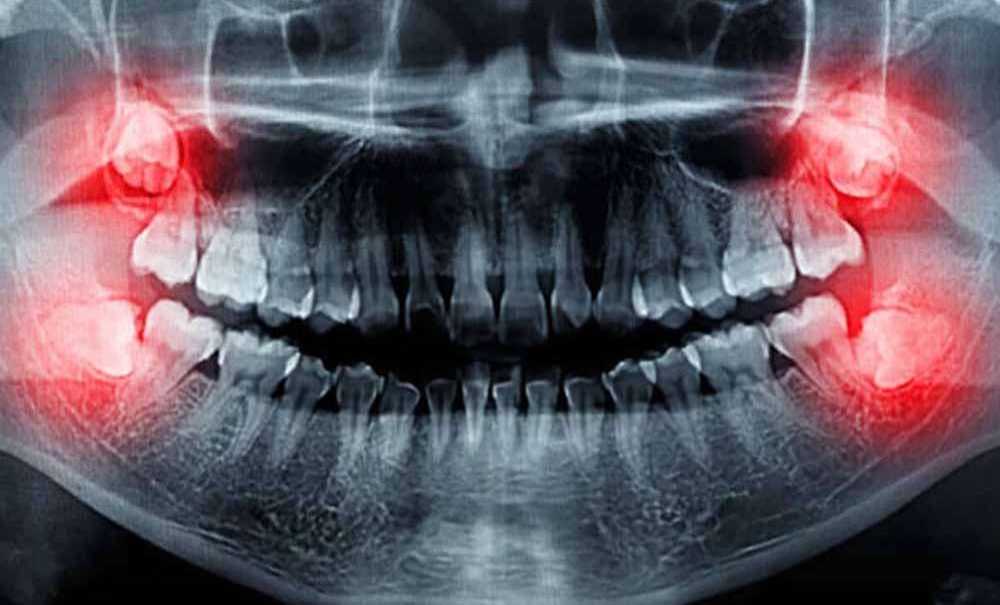

Gömülü dişlerin vereceği rahatsızlıkları dile getiren Diş Hekimi Kemal Kavut “Gömülü dişler ( yarı veya tam gömülü) hastalarda çeşitli rahatsızlıklara sebep olurlar. Gömülü dişler, çene arkı içerisinden geçen damar sinir paketine ve komşu dişlere baskı yaparak ağrıya sebebiyet verirler” dedi.

“Gömülü dişler komşu dişlere baskı yaparak diş dizisinin düzenini bozabilir ve dişlerde eğrilikler, çapraşıklık yapabilir” diyen diş hekimi Kemal Kavut, “Özellikle ortodontik tedavi görmüş ya da görmekte olan hastalarda, gömülü dişler diş hekiminin uygulayacağı ortodontik kuvvete, ters yönde kuvvet uygulayıp, tedavi ile düzeltilmiş diş dizisinin bozulmasına sebep olup, ortodontik tedavi başarısını ortadan kaldırabilir. Bazen gömülü dişler, kısmen ağız ortamına sürerek yarı gömülü halde kalabilirler. Yarısı süren bu dişler ile dişin yarısını örten dişeti arasında bakterilerin yerleşeceği derin enfeksiyonel cepler oluşur” dedi.

Konuşmasını sürdüren Diş Hekimi Kemal Kavut, “Bu ekfeksiyonel ağrı, şişlik ve ağız açma zorluğu gibi problemler oluşturabilir. Böyle durumlarda hasta mutlaka diş hekimine başvurmalıdır. Bu durumda diş hekimi hastaya mevcut enfeksiyonu gidermek için antibiyotik tedavisi uygulayacaktır ve randevu verecektir. Daha sonra gömülü dişin pozisyonunu görmek için röntgen alacaktır. Gömülü dişler çevrelerindeki diğer dişlerin kemik dokusunu zayıflatır ve komşu dişlerin dişetlerinde hastalığa sebep olabilir. Ayrıca komşu dişlerin köklerine basınç yaparak bu dişlerin köklerinde erimeye sebep olabilir. Gömülü dişlerden kaynaklı kist veya tümörler de ortaya çıkabilir” ifadelerini kullandı.